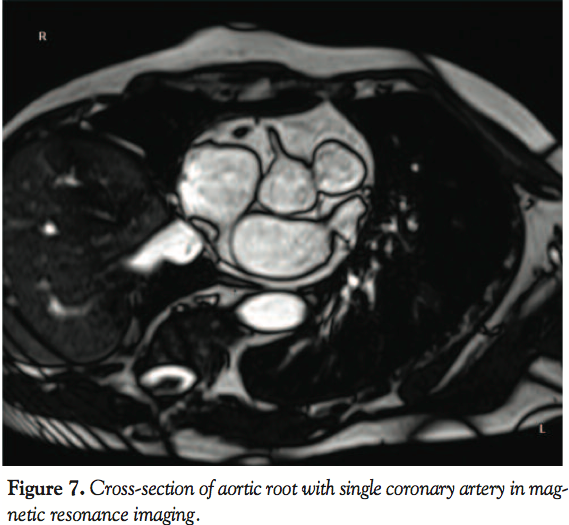

On the control angiography, it was apparent that the patient had single coronary vessel that originated in the right sinus of Valsalva. The LM ostium was absent. The single artery showed a typical course of a dominant RCA and created branches to the circumflex artery (LCX) and the left anterior descending (LAD) branch. The secondary vessels clearly branched toward the base of the heart and they showed no significant arteriosclerotic lesions. Echocardiography found no concomittant

structural heart anomalies. After 9 months, the patient remained asymptomatic and the early submaximal exercise ECG test was negative. Magnetic resonance imaging (MRI) confirmed both absence of LM and presence of single coronary artery (SCA) originating from the right sinus of Valsalva (Figure 7).

artery in very symptomatic pediatric patients. LM coronary atrophy/agenesis has been described in the literature and often coexists with other multiple congenital anomalies.3,7-9,12 It is characterized by either total absence of LM ostium or presence of its remnant that has no contact with the rest of the left coronary system. Left-sided arteries often have normal distribution and are supplied with blood from the RCA by multiple collaterals. LM agenesis is an extremely rare entity and may be found in 0.0024%-0.044% of the population.6 SCA with agenesis of aorto-coronary ostium of either RCA or LM has been described, but is very rare.4,5,12 In such cases, arteries create a single system where vessel continuity and integrity are intact (Figure 7).